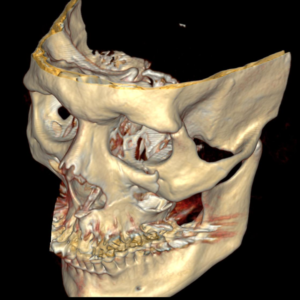

O diagnóstico é feito pelo exame físico dos ferimentos e, nos casos de suspeita de fratura, deve se associar radiografias e tomografias computadorizadas. Esse avaliação poderá ser feita no hospital (se o paciente estiver internado) ou no consultório odontológico. O primeiro passo no tratamento é garantir a vida do paciente. O profissional deve garantir que o paciente esteja respirando bem e sem lesões graves que podem levar a morte rapidamente (como hemorragias severas, obstrução de vias aéreas e lesões de órgãos vitais)

A maioria dos ferimentos simples na pele pode ser tratada com anestesia local, limpeza da lesão e sutura. As fraturas da face e lesões complexas são tratadas sob anestesia geral. Os ossos quebrados são restaurados utilizando-se, geralmente, mini-placas e parafusos de titânio (que são biocompatíveis e não sofrem rejeição) que facilitam a recuperação e cicatrização óssea e dos tecidos